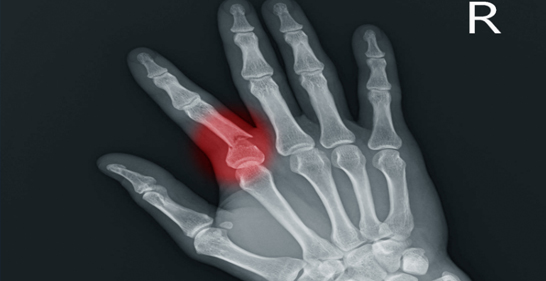

4. Finger Fracture

A break in any of the small bones of the fingers.

Icon Cause: Sports injuries, falls, or crushing accidents.

Icon Symptoms: Swelling, tenderness, difficulty moving the finger.

Icon Treatment: Splinting, taping, or surgery if the fracture is severe.